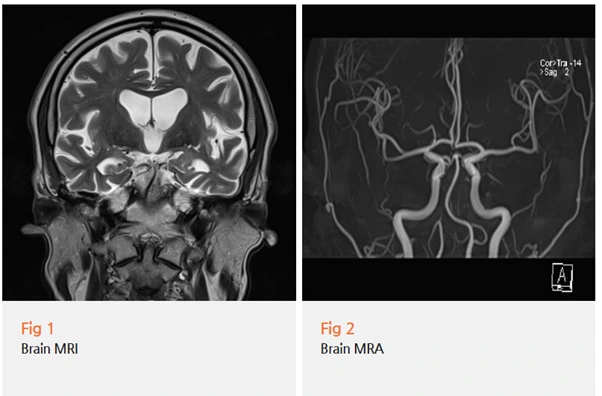

이 환자분도 3.0T 뇌 MRI와 뇌 MRA 검사를 당일에 바로 진행했어요.

다행히 뇌출혈이나 뇌경색, 종양 같은 위험한 소견은 없었어요.

하지만 알츠하이머 치매를 의심할 만한 뇌 위축 소견이 보였어요.

특히 해마 부위의 위축이 관찰됐는데,

해마는 기억을 담당하는 중요한 부위거든요.